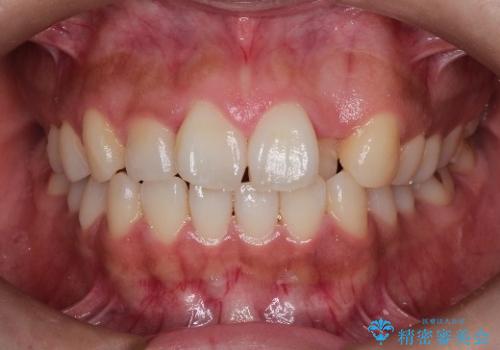

八重歯をマウスピース矯正で治療し、レーザーホワイトニングを行った症例

- 主訴:「右上犬歯を引っ込めて、歯並びをキレイにしたい」

右上の八重歯を気にされてご来院されました。結婚式を控えていたため挙式にまでに可能な限りキレイにしたいとのことでした。

また、ホワイトニングも一緒にご希望されたため、挙式のタイミングに合わせてレーザーホワイトニングを施術させていただきました。

右上の犬歯の歯茎は矯正前から退縮を起こしていましたが、矯正後もその退縮に関しては変化がありませんでした。今回は患者様が歯肉退縮に関しては治療をご希望ではありませんでしたが、当院ではこのように歯茎が下がり露出した根面を、歯茎を移植することでカバーし見た目を改善する手術を行っています。